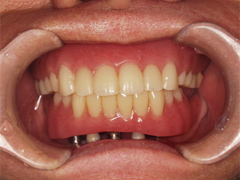

手術から7ヵ月後、一回目の仮歯の状態です。

歯茎の腫れも治まってきました。

まだ歯茎の状態は年々変化していきますので仮歯は数回作り変え、経過を観察後、最終的な固定的ブリッジが入ります。